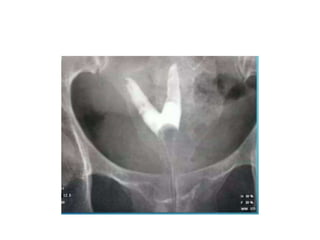

Unicornuate uterus

Didelphys uterus

Bicornuate uterus

SEPTATE UTERUS

• Intercornual angle- <75

• Intercornual distance <2cm

• Intercornual angle ->105

• Intercornual distance 2-4cm

Arcuate uterus

Hypoplastic uterus

Pseudo-unicornuate/true unicornuate

SEPTATE UTERUS • Intercornualangle- <75 • Intercornual distance <2cm BICORNUATE UTERUS • Intercornual angle ->105 • Intercornual distance 2-4cm